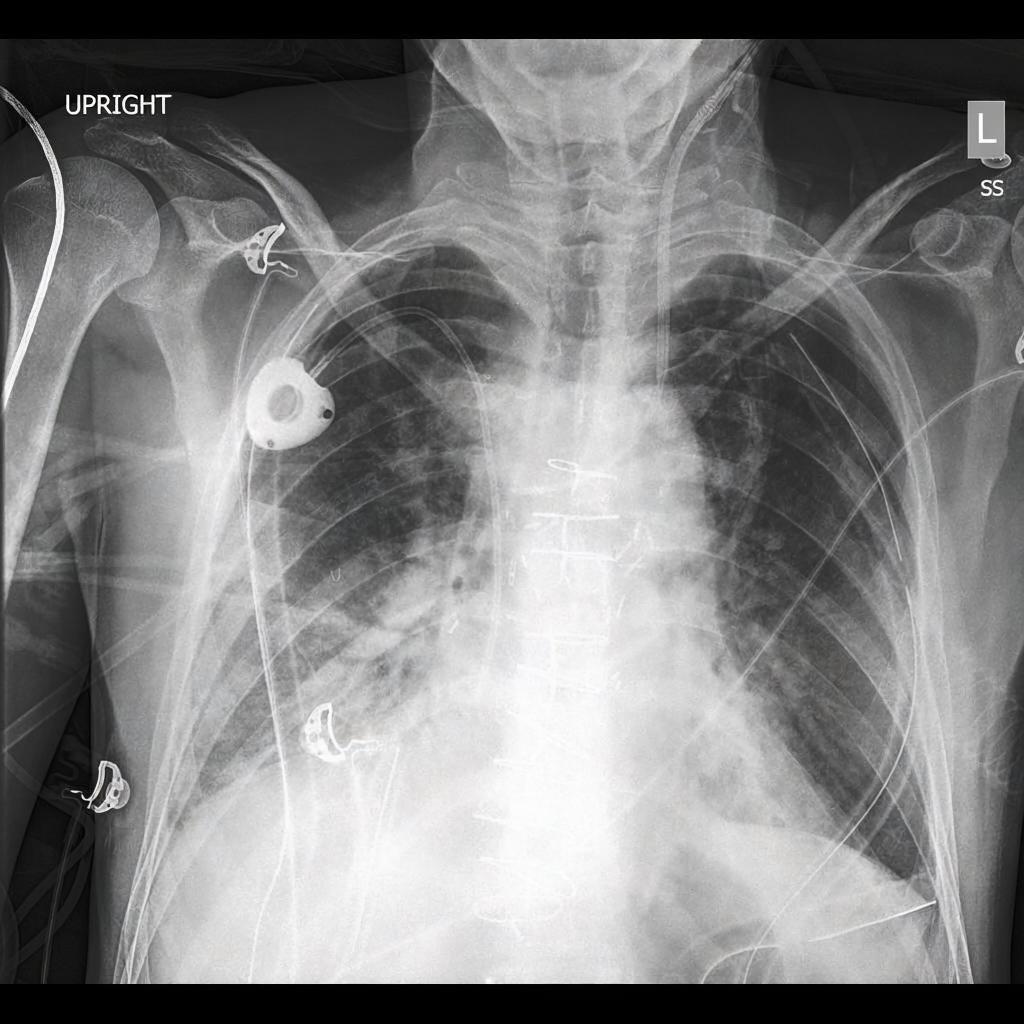

Diffusion models have recently gained significant traction due to their ability to generate high-fidelity and diverse images and videos conditioned on text prompts. In medicine, this application promises to address the critical challenge of data scarcity, a consequence of barriers in data sharing, stringent patient privacy regulations, and disparities in patient population and demographics. By generating realistic and varying medical 2D and 3D images, these models offer a rich, privacy-respecting resource for algorithmic training and research. To this end, we introduce MediSyn, a pair of instruction-tuned text-guided latent diffusion models with the ability to generate high-fidelity and diverse medical 2D and 3D images across specialties and modalities. Through established metrics, we show significant improvement in broad medical image and video synthesis guided by text prompts.

In this work, we focus on the ability of LDMs to generate novel datasets to overcome class imbalances traditionally associated with medical data, and potentially reduce the need for manual annotation of medical 2D and 3D data. We present MediSyn, a pair of text-guided latent diffusion models for broad medical 2D and 3D modality synthesis. To overcome the scarcity of labelled medical data, we leverage a vast corpus of more than 5 million image-caption pairs and 100,000 video-caption pairs collected from the public domain across numerous medical specialties, and integrate comprehensive natural language annotations to develop a pair of versatile diffusion models for the medical domain.

Our work, akin to Sagers et al. and Chambon et al. focuses on synthesizing multi-class medical datasets through text prompts. In their work, Chambon et al. adapt a pre-trained LDM, Stable Diffusion, on a corpus of chest x-rays (CXR) and their corresponding radiology reports to generate CXR displaying different disease states [29]. Similarly, Sagers et al. use DALL-E to synthesize skin lesions across all Fitzpatrick skin types [30].

Our findings demonstrate Medisyn’s remarkable ability to generate high-fidelity and diverse medical images, image sequences and volumetric scans across various medical subspecialties and imaging modalities. Other medical text-driven diffusion models, such as TauPETGen [42] for tau PET images and GenerateCT [43] for chest CT volumes, have proven successful in generating high-quality images that accurately depict anatomical features and clinical conditions. However, these models are constrained to a single imaging modality and anatomical region, thereby restricting their applicability. Moreover, they were trained on relatively small datasets sourced from a limited number of institutions, which could lead to more biased outputs. In contrast, Medisyn, having been trained on one of the largest publicly accessible medical image and video datasets to date, is equipped to synthesize data that cover numerous medical disciplines, population groups, and disease states. Leveraging our two models, we can synthesize new medical datasets as well as augment existing ones, potentially improving a wide array of medical machine learning tools, both general and specialized. Additionally, our models can minimize the need to repeatedly fine-tune on specific datasets for generating different imaging modalities, thus reducing computational costs for academic labs.